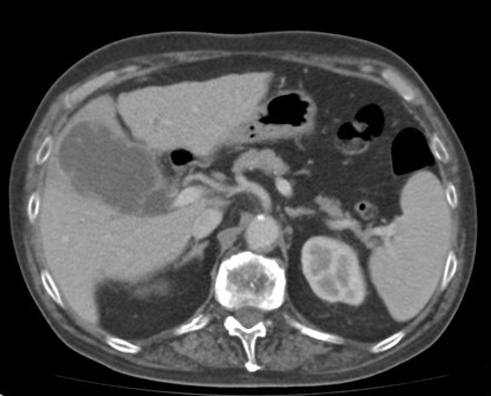

Cholecystite

lithiasique aigue : Vesicule biliaire est distendue

, image epaissisement et rehaussement hyperdense de la paroi

avec epanchement perivesiculaire . La lithiase

hyperdense situe a infundibulum . Image

radiologique TDM + contrast en coupe axiale |